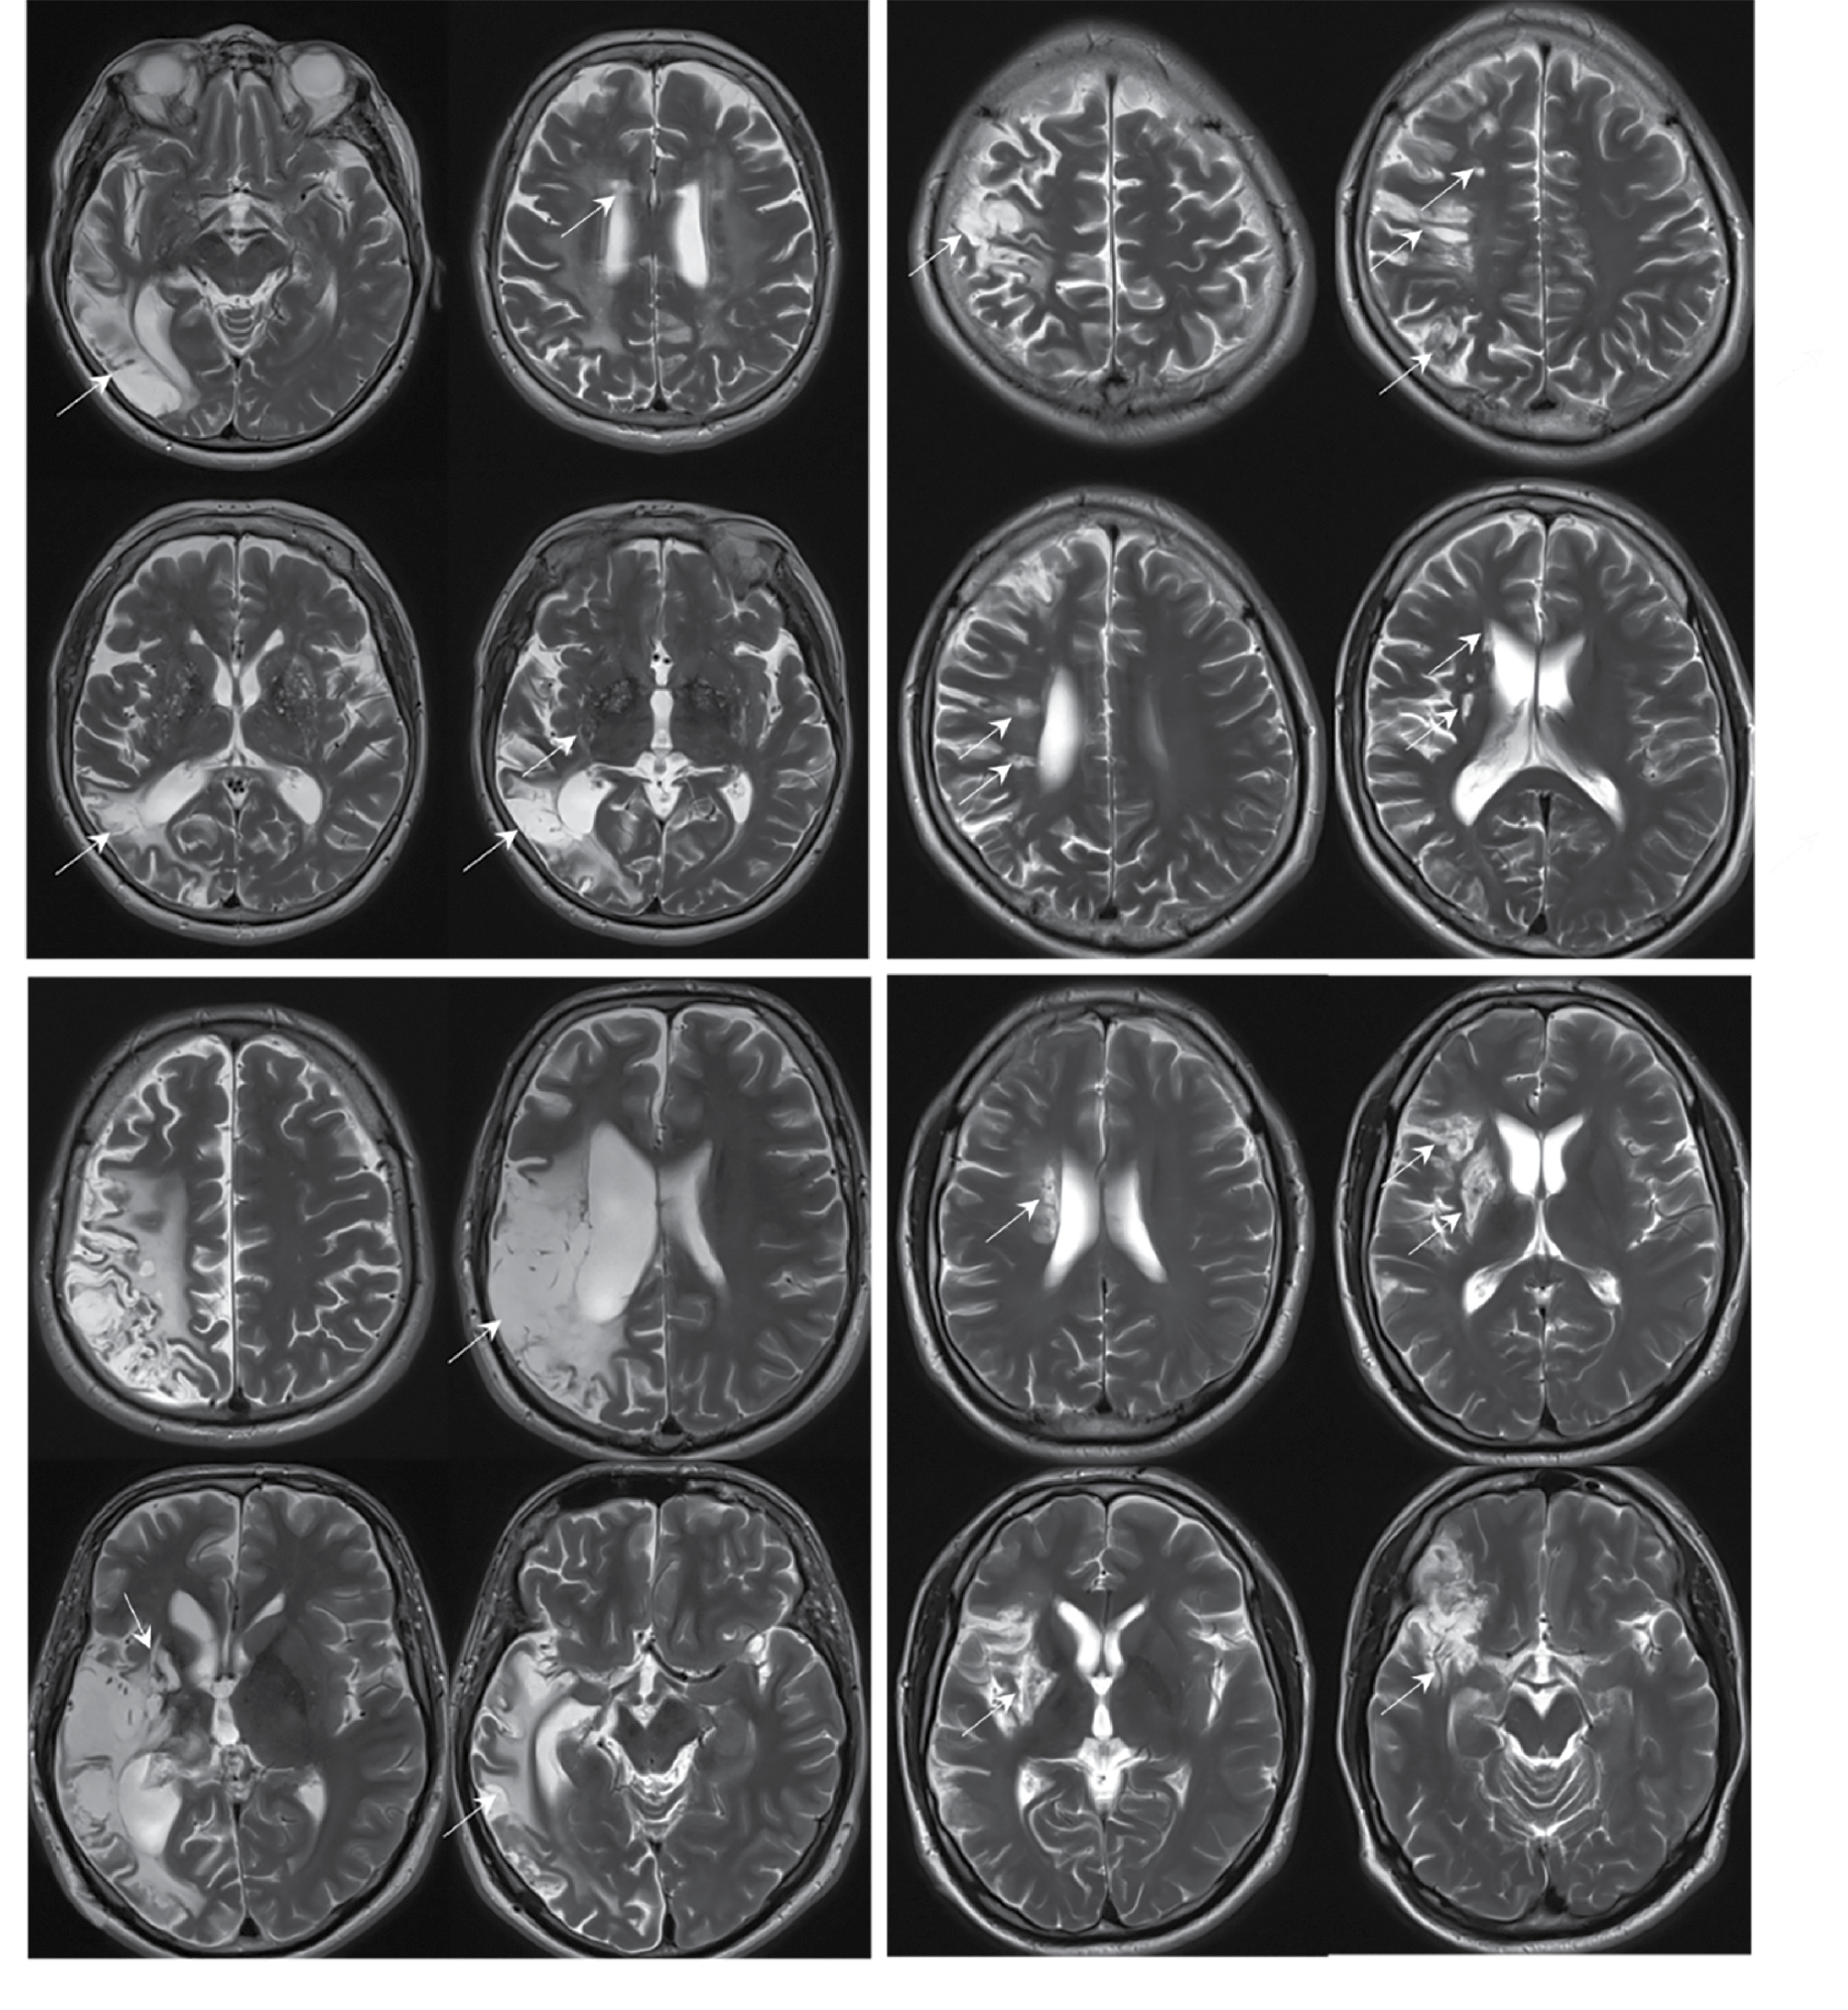

Эссенциальная тромбоцитемия

Характерными нейровизуализационными признаками НМК при ЭТ являлись массивные постинфарктные изменения с вовлечением коры, подлежащего и глубокого белого вещества, базальных ганглиев с частотой встречаемости 67%. В 26% случаев НМК развивалось на фоне тромботической окклюзии внутренней сонной артерии с последующим формированием массивного очага ишемии в веществе мозга. В большинстве случаев клиническая картина была представлена острым началом с развитием грубого неврологического дефицита. В 26% случаев постинфарктные изменения в веществе головного мозга встречались в бассейне вертебрально-базилярной системы, в 74% — в каротидном бассейне. В 33% случаев последствия НМК привели к развитию стойкой утраты дееспособности и инвалидности (средний возраст пациентов — 32 года).

Ведущим нейровизуализационным паттерном последствий НМК при ЭТ был большой объём поражения вещества мозга с корково-подкорковой локализацией (рис. 4).

Рис. 4. МРТ головного мозга пациентов с ЭТ — Т2-взвешенные изображения в аксиальной плоскости.

Во всех случаях визуализируются массивные постинфарктные изменения с вовлечением коры, подлежащего и глубокого белого вещества, а также базальных ганглиев (постинфарктные изменения указаны стрелками).

Fig. 4. Brain MRI of patients with ET; axial plane T2-weighted images.

In all cases, massive post-infarction changes are found in the cortex, underlying and deep white matter, and basal ganglia (post-infarction changes are indicated by arrows).